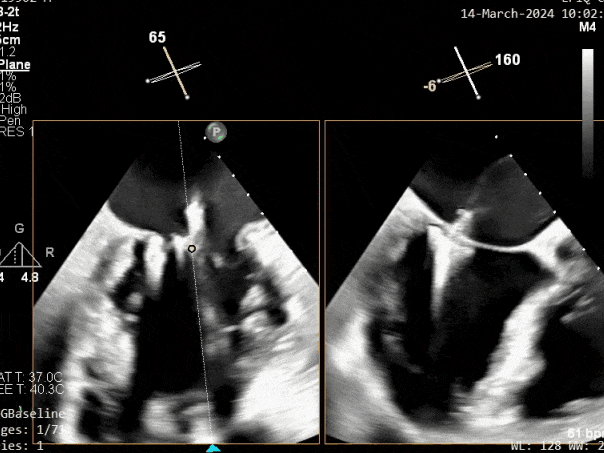

瓣膜夹释放前评估,二尖瓣反流减轻

瓣膜夹释放前评估,二尖瓣平均跨瓣压差及瓣口面积

释放瓣膜夹后评估,二尖瓣呈双孔,外侧仍有残余反流